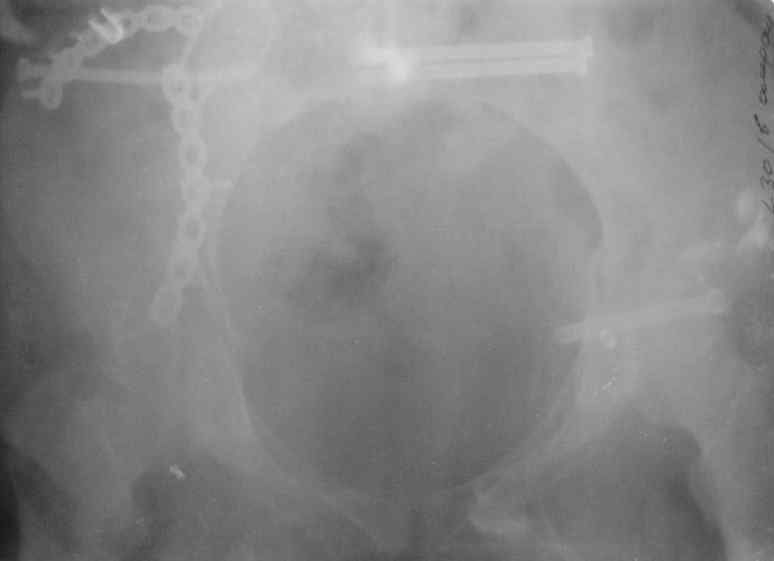

Здравствуйте, коллеги. Какие будут мнения по поводу лечения представляемой больной?

Молодая девушка 19 лет, травма 1 год назад, тогда же прооперирована.

В настоящее время имеются ноющие боли в области крестца слева, нарушение походки, ощущение неуверенности, слабости в левой нижней конечности, неврологически -непостоянные парестезии в левой нижней конечности. Ходит с дополнительной опорой, страдает от ожирения.

Какова по вашему будет оптимальная тактика в отношении несращения крестца? Замена винтов на более длинные с коррекцией их положения+ туннелизация зоны нестращения, открытое вмешательство с костной аутопластикой или еще какие варианты?

В приложении снимки при поступлении и послеоперационные год назад.